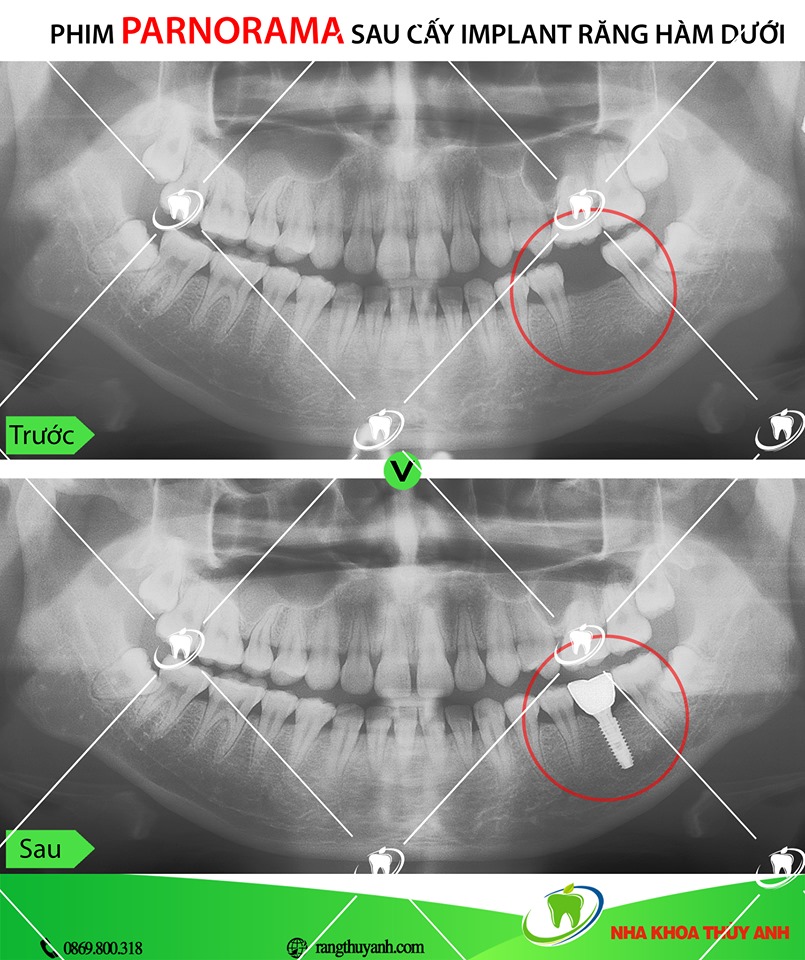

Cắm implant là một phương pháp phục hình răng đòi hỏi kỹ thuật, trình độ cao, vì vậy bác sĩ cần có chuyên môn và giàu kinh nghiệm. Trong đó việc chẩn đoán chính xác ban đầu là bước không thể thiếu.

Cấy implant là phương pháp trồng răng tốt nhất hiện nay. Implant gồm có 3 phần, phần thứ nhất là chân răng, được cấy thẳng vào xương hàm thay thế chân răng mất. Phần thứ 2 là trụ phục hình abutment đó là phần kết nối với chân răng và nhô lên khỏi lợi để răng sứ bọc lên đó. Phần thứ 3 là răng sứ, sẽ là 1 chụp sứ hoặc hàm giả gắn lên abutment.

Về định nghĩa chúng ta có thể hình dung implant là 1 vít (chân răng nhân tạo) làm bằng chất liệu titanium (có tính tương hợp sinh học với cơ thể người) được cấy vào xương để thay thế chân răng mất, nhằm nâng đỡ phục hình răng sứ. Như vậy bản chất của quá trình thực hiện implant chính là cấy ghép trên cơ thể người, chính vì vậy để sử dụng được loại răng này cần có một thời gian nhất định cho vít implant ổn định trong xương hàm, thời gian trung bình cho quá trình là khoảng 3 tháng, tuy nhiên vấn đề còn phụ thuộc nhiều yếu tố chuyên môn khác nữa.